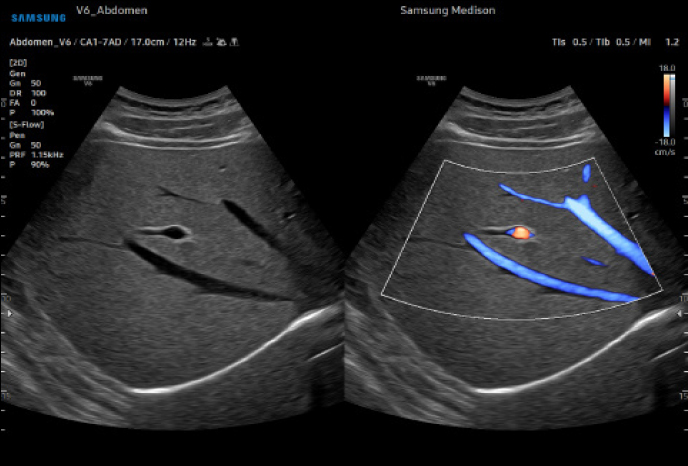

하이앤드 초음파 장비를

활용한 정밀 심장 검사

심장 질환 진단에서 가장 중요한 것은 ‘심장의 상태를 얼마나 정확하게 볼 수 있느냐’입니다. 저희 센터는 대학병원급 하이앤드 초음파 장비를 도입하여, 실시간 3D 렌더링으로 정밀 진단이 가능하며, 심장의 구조·혈류·기능을 실시간 고해상도로 관찰합니다.

미세한 판막 움직임, 혈류 속도 변화, 심방·심실 크기와 수축력까지 정밀하게 분석할 수 있어, 심장질환의 조기 발견과 치료 계획 수립에 큰 차이를 만듭니다.